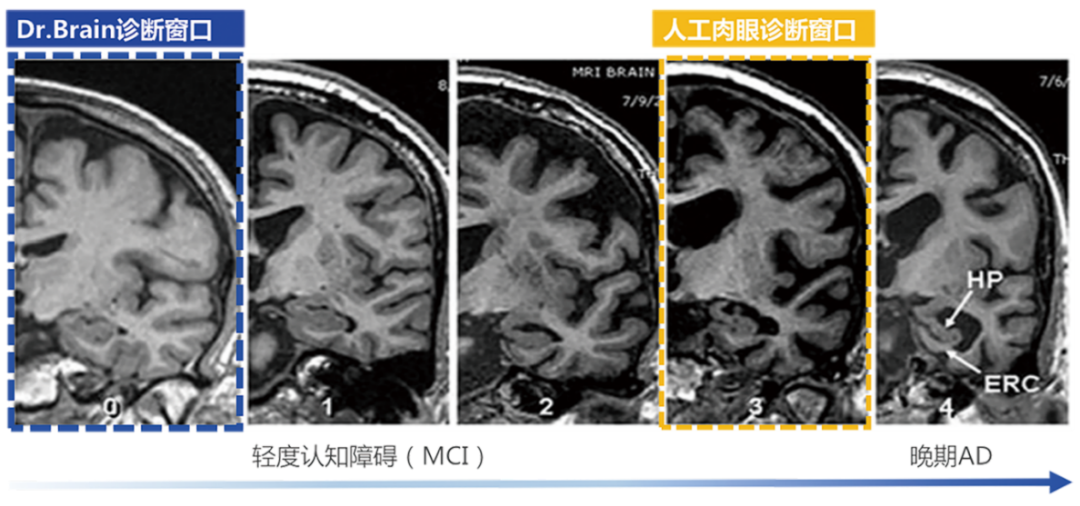

超早期的診斷

利用AI算法識(shí)別肉眼難以發(fā)現(xiàn)的腦結(jié)構(gòu)超早期的細(xì)微改變,大幅提前疾病診斷窗口

針對(duì)AD的治療,國(guó)際上已批準(zhǔn)的AD藥物基本都是對(duì)早期AD患者在延緩病程發(fā)展上有顯著療效,但對(duì)于晚期患者,即使檢出也是療效甚微?!栋柎暮D?chuàng)新藥物臨床試驗(yàn)中國(guó)專家共識(shí)》強(qiáng)調(diào)AD應(yīng)著力于早期發(fā)現(xiàn)和預(yù)防,而臨床現(xiàn)狀是AD的診斷率低且漏診率高。因此,AD的早篩、早診對(duì)延緩該疾病的發(fā)展至關(guān)重要。臨床中對(duì)AD診斷首選的影像學(xué)檢查方法是磁共振成像 (Magnetic Resonance ImagingMRI) ,但臨床上大多數(shù)醫(yī)生認(rèn)為AD病人的腦結(jié)構(gòu)異常變化發(fā)生較晚,而今借助AI算法,其實(shí)醫(yī)生能在高維空間捕捉到宏觀和微觀、具體和抽象的腦結(jié)構(gòu)特征,可以輔助醫(yī)生利用MRI結(jié)構(gòu)影像在早期精準(zhǔn)診斷AD性質(zhì)的腦結(jié)構(gòu)異常改變。因此,人工智能應(yīng)用于影像診斷和疾病篩查診斷近年來(lái)變?yōu)槿蜥t(yī)療器械業(yè)界的趨勢(shì)與熱點(diǎn),其中,在腦部疾病診療領(lǐng)域,即有可能改變將來(lái)的AD診療路徑。